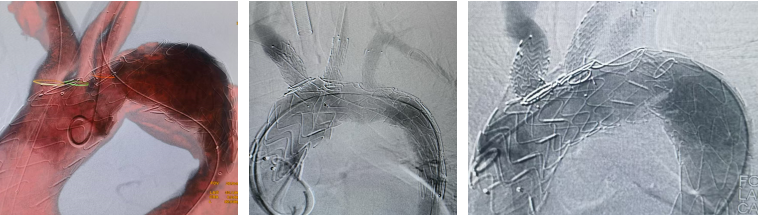

商业分支支架:新时代的“利器”

随着器械发展,多家企业推出商业化的分支支架系统,为弓部修复提供了更标准化、便捷化的选择。

(一)TBE支架

★ 病例3

27岁男性,急性主动脉夹层,破口紧邻左锁骨下动脉。

手术亮点:

TBE支架采用“导丝直出”设计,释放后无需解缠绕,操作简便;

支架柔顺性好,即使成角90°–180°也不打折;

顺应弓部运动,长期通畅率良好,五年随访结果优异。

(二)ZIPPER支架系统

团队在全球范围内率先完成6例ZIPPER支架植入,其中前三例均为该中心开展。

植入仅需对准左颈总动脉,导丝进入无名动脉后即可释放;

手术时间从初期的2小时40分钟缩短至42分钟,流程大幅简化。